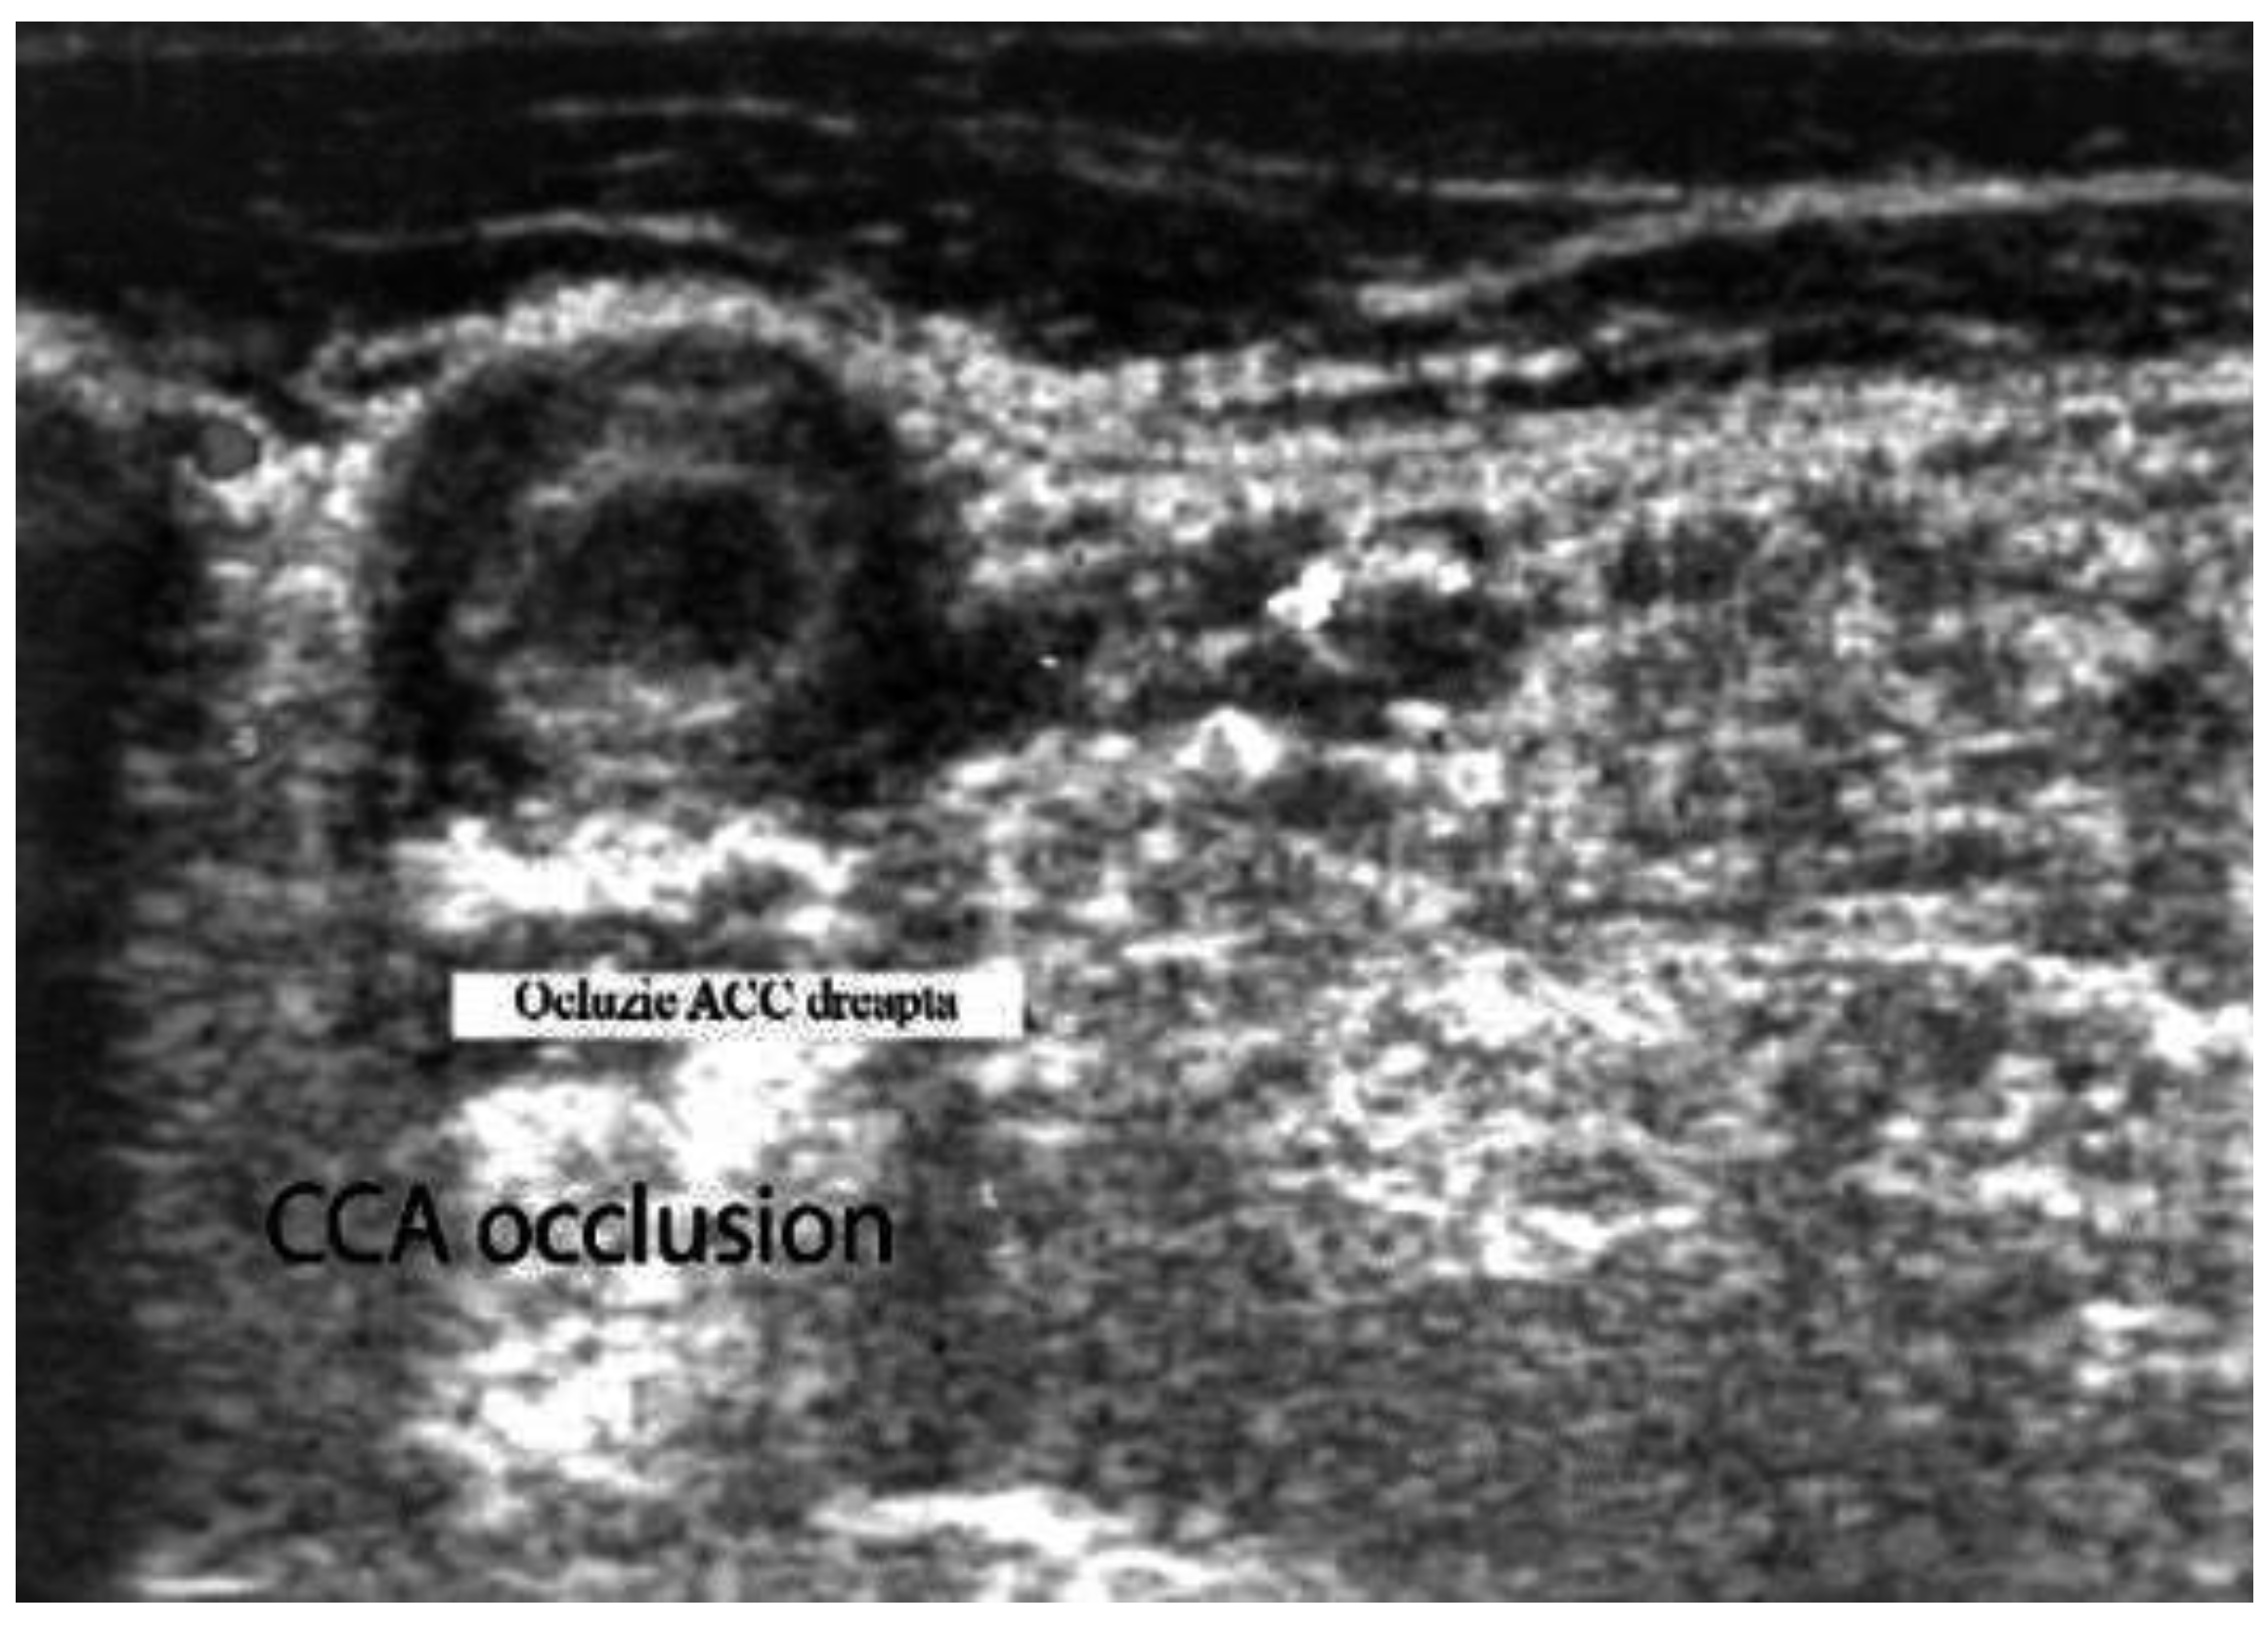

- Acute occlusions, wherein the US image is similar to that of acute embolism in different other vessels, with lack of color Doppler signals (even with low pulse repetition frequency and high color gain) in a visible artery lumen filled with hypoechoic material (cloth) [30,31,32,33,34,35,36,37,38,39,40,41].